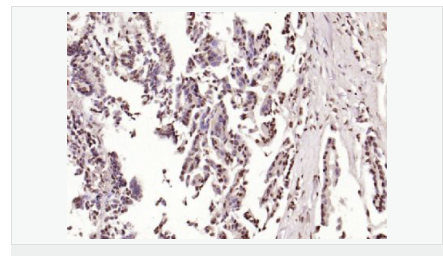

| 英文名稱(chēng) | phospho-HSP70 (Tyr611) |

| 中文名稱(chēng) | 磷酸化熱休克蛋白-70抗體 |

| 別 名 | HSP70 (phospho Tyr611); HSP70 (phospho Y611); p-HSP70 (Tyr611); p-HSP70 (Y611); HSP70; HSP-70; HSP 70; Heat shock 70 kDa protein 1; heat shock 70kDa protein 1A; Heat shock 70kDa protein 1B; Heat shock induced protein; heat shock protein 70; HSP70 1; HSP70 2; HSP70.1; HSP72; HSPA1; HSPA1A; HSPA1B; XXbac BCX40G17.3 001; Heat shock 70 kDa protein 1A/1B; HSP71A_HUMAN; Hspa1a; Hsp70-1; HSP72; Hspa1; Hspa1b; Heat shock 70 kDa protein 1A/1B; shock 70 kDa protein 1/2; HSP70-1/HSP70-2; HSP70.1/HSP70.2. |

| 產(chǎn)品類(lèi)型 | 磷酸化抗體 |

| 抗體來(lái)源 | Rabbit |

| 克隆類(lèi)型 | Polyclonal |

| 交叉反應 | Human, Mouse, Rat, (predicted: Dog, Pig, Rabbit, Guinea Pig, ) |

| 產(chǎn)品應用 | ELISA=1:5000-10000 IHC-P=1:100-500 IHC-F=1:100-500 Flow-Cyt=1μg/Test ICC=1:100 IF=1:100-500 (石蠟切片需做抗原修復) not yet tested in other applications. optimal dilutions/concentrations should be determined by the end user. |

| 分 子 量 | 70kDa |

| 細胞定位 | 細胞漿 |

| 免 疫 原 | KLH conjugated Synthesised phosphopeptide derived from human HSP70 around the phosphorylation site of Tyr41:GL(p-Y)QG |

| PubMed | PubMed |

| 產(chǎn)品介紹 | This intronless gene encodes a 70kDa heat shock protein which is a member of the heat shock protein 70 family. In conjuction with other heat shock proteins, this protein stabilizes existing proteins against aggregation and mediates the folding of newly translated proteins in the cytosol and in organelles. It is also involved in the ubiquitin-proteasome pathway through interaction with the AU-rich element RNA-binding protein 1. The gene is located in the major histocompatibility complex class III region, in a cluster with two closely related genes which encode similar proteins. [provided by RefSeq, Jul 2008]. Function: In cooperation with other chaperones, Hsp70s stabilize preexistent proteins against aggregation and mediate the folding of newly translated polypeptides in the cytosol as well as within organelles. These chaperones participate in all these processes through their ability to recognize nonnative conformations of other proteins. They bind extended peptide segments with a net hydrophobic character exposed by polypeptides during translation and membrane translocation, or following stress-induced damage. In case of rotavirus A infection, serves as a post-attachment receptor for the virus to facilitate entry into the cell. Subunit: Component of the CatSper complex. Identified in a mRNP granule complex, at least composed of ACTB, ACTN4, DHX9, ERG, HNRNPA1, HNRNPA2B1, HNRNPAB, HNRNPD, HNRNPL, HNRNPR, HNRNPU, HSPA1, HSPA8, IGF2BP1, ILF2, ILF3, NCBP1, NCL, PABPC1, PABPC4, PABPN1, RPLP0, RPS3, RPS3A, RPS4X, RPS8, RPS9, SYNCRIP, TROVE2, YBX1 and untranslated mRNAs. Interacts with TSC2. Interacts with IRAK1BP1. Interacts with TERT; the interaction occurs in the absence of the RNA component, TERC, and dissociates once the TERT complex has formed. Interacts with DNAJC7. Interacts with CHCHD3. Subcellular Location: Cytoplasm. Note=Localized in cytoplasmic mRNP granules containing untranslated mRNAs. Tissue Specificity: HSPA1B is testis-specific. Similarity: Belongs to the heat shock protein 70 family. SWISS: P0DMV8 Gene ID: 3303 Database links: Entrez Gene: 3303 Human Entrez Gene: 3304 Human Entrez Gene: 15511 Mouse Entrez Gene: 193740 Mouse Omim: 140550 Human Omim: 603012 Human SwissProt: P0DMV8 Human SwissProt: P0DMV9 Human SwissProt: P17879 Mouse SwissProt: Q61696 Mouse Unigene: 274402 Human Unigene: 719966 Human Unigene: 728810 Human Unigene: 1950 Rat Unigene: 228225 Rat Important Note: This product as supplied is intended for research use only, not for use in human, therapeutic or diagnostic applications. |